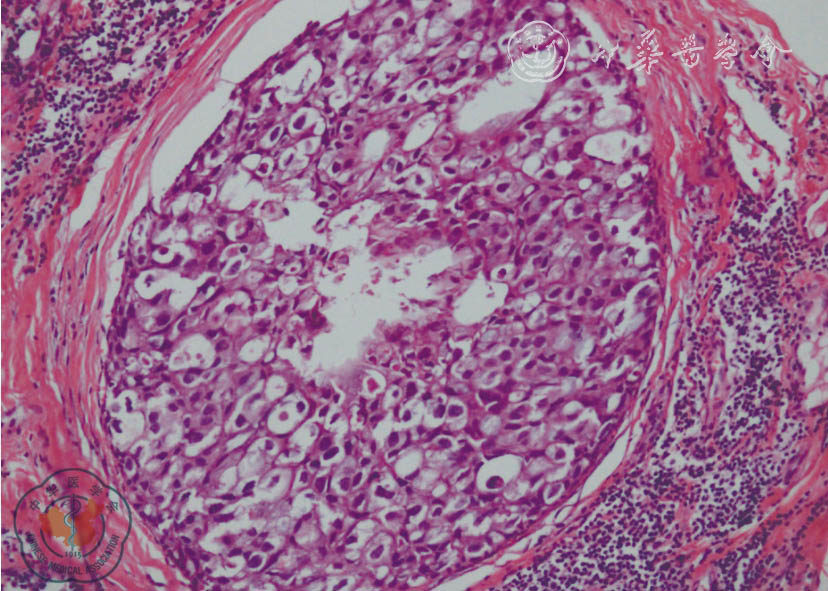

图2 1 例乳腺导管内癌病理图(HE 染色 ×100)

导管腔内可见异型增生上皮细胞,形态、大小相对一致,细胞核有明显异型,中央区见少许坏死,导管周围间质反应性增生伴淋巴细胞浸润。